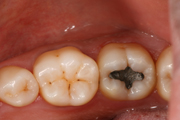

Mit aktuellen Kunststoffmaterialen lassen sich ästhetische und langlebige Füllungen realisieren. Sie sind in verschiedenen Weißtönen erhältlich und können so individuell dem Zahn angepasst werden, wie an den Fotos oben zu sehen: hier wurde eine Amalgamfüllung durch eine Kunststoff-Füllung ersetzt. Ein weiterer Vorteil besteht in der zahnsubstanzschonenden Behandlung. Es muss nur wirklich kariöses Material vom Zahn abgeschliffen werden. Die korrekte Verarbeitung dieser Materialien ist sehr aufwendig, verbunden mit hohen Materialkosten. Die gesetzlichen Krankenkassen übernehmen die Kosten für Kunststoff-Füllungen im Backenzahnbereich nur bei nachgewiesener Allergie gegen Amalgam (Allergiepass). Je nach Größe der Kunststofffüllung fällt deshalb eine Zuzahlung für Sie an.